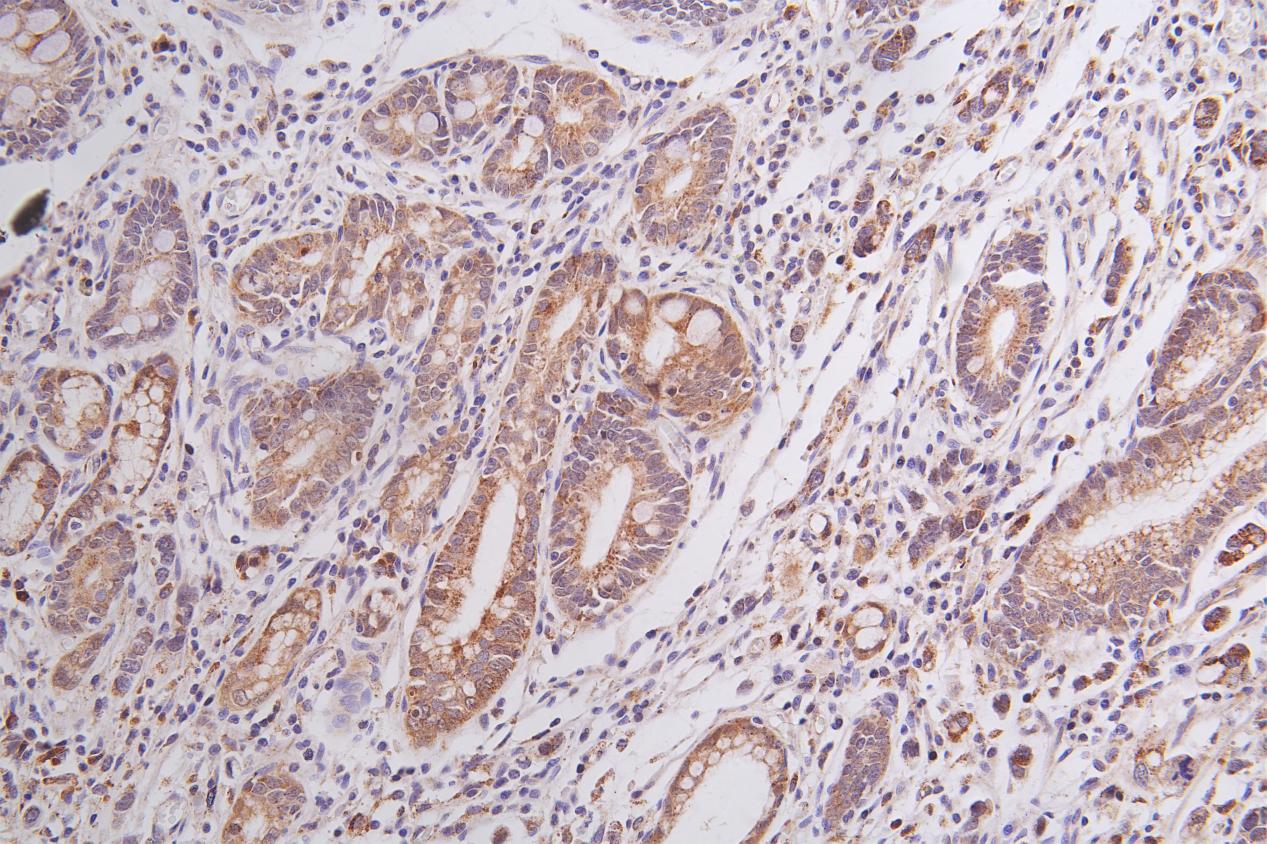

IHC image of CSB-PA018238ESR2HU diluted at 1:50 and staining in paraffin-embedded human gastric cancer performed on a Leica BondTM system. After dewaxing and hydration, antigen retrieval was mediated by high pressure in a citrate buffer (pH 6.0). Section was blocked with 10% normal goat serum 30min at RT. Then primary antibody (1% BSA) was incubated at 4°C overnight. The primary is detected by a Goat anti-rabbit polymer IgG labeled by HRP and visualized using 0.05% DAB.